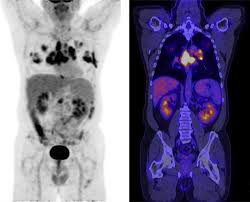

PET의 또 다른 장점으로 거의 모든 종류의 암을 찾아낼 수 있다는 것이라고 한다. 일반적으로 암세포는 포도당 대사가 높기 때문이라고 한다.

또 머리끝에서 발끝까지 촬영해 어느 곳에 있는 암이라도 잡아낸다. 다시 말하면 사각지대가 없다고나 할까? 이미 일본에서는 이 방법으로 암을 검진하는 프로젝트를 성황리에 진행하고 있다고 한다.

그러나 일본의 경우 증상이 없는 PET 검진자의 1∼2%에서 암을 찾아내고 있다고 한다. 또 이미 암을 진단받은 후에도 전신 PET를 해 보면 5∼7%에서 숨어 있는 다른 암을 찾을 수 있다고 한다.

물론 고령의 할아버지와 할머니가 많지만 우리나라 남자의 3분의1에서 2분의1이 일생동안 결국은 암에 걸린다는 통계자료를 볼 때 수긍이 된다. 일본 자료에 의하면 갑상선암, 폐암, 대장암 등이 잘 발견되고 있다고 한다.